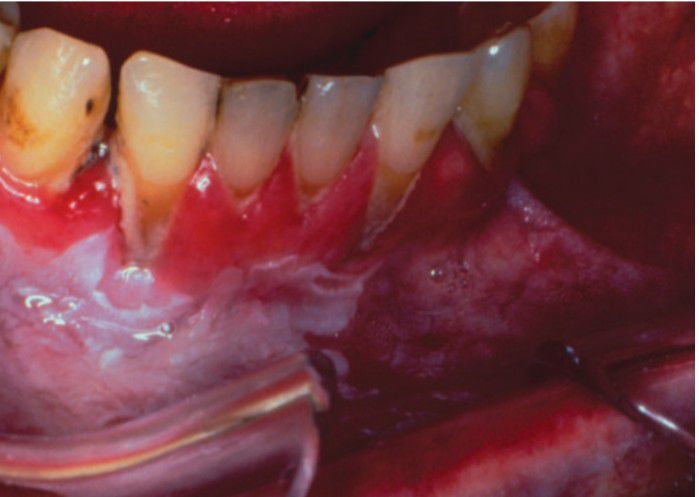

Snuff dipper's pouch

Snuff pouch showing extensive periodontal tissue destruction and a thickened area of leukoplakia.